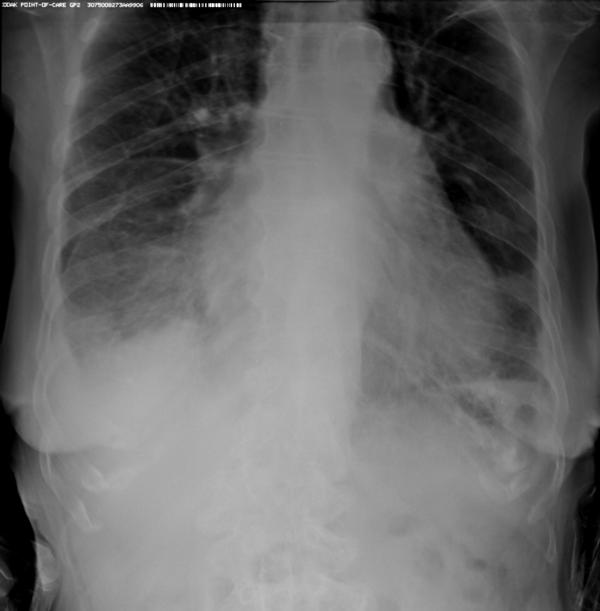

Второй наиболее частой причиной, по которой выполняется рентген грудной клетки, является травма груди с подозрением на перелом рёбер. Может показаться, что ушиб грудной клетки является несерьезным основанием, чтобы обратиться к врачу и сделать рентген. Однако приглушая боль приёмом обезболивающих препаратов, можно пропустить ряд опасных осложнений. Сломанные рёбра могут ранить легкое и вызвать пневмоторакс, т.е. скопление воздуха, или гемопневмоторакс, т.е. скопление крови и воздуха в грудной полости. Перелом трех и более рёбер может вызвать серьёзные дыхательные нарушения, что особенно опасно у пожилых пациентов. Поэтому не стоит рисковать здоровьем и необходимо сразу обратиться к врачу. Пациенты, обратившиеся в наш медицинский центр "Ваше Здоровье", смогут получить весь комплекс необходимых лечебно-диагностических мероприятий, в т.ч. рентген на дому.